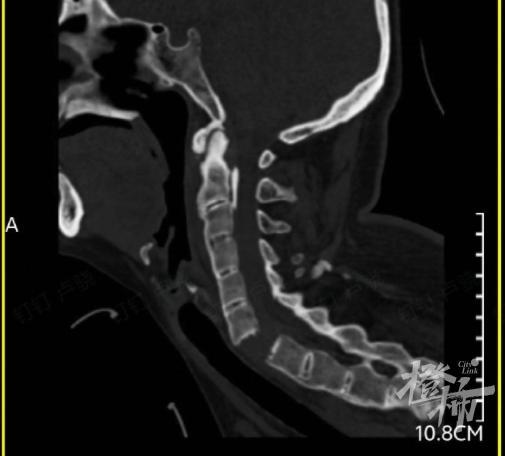

当时,刘女士就出现颈部疼痛、四肢无力的症状,紧接着发现自己全身不能活动。随后,她被紧急送往附近的医院救治,通过颈椎影像检查后发现,刘女士颈椎 6-7 节完全断离,颈椎骨折造成脊髓损伤,导致全身瘫痪。

(检查发现,刘女士的颈椎完全断离)